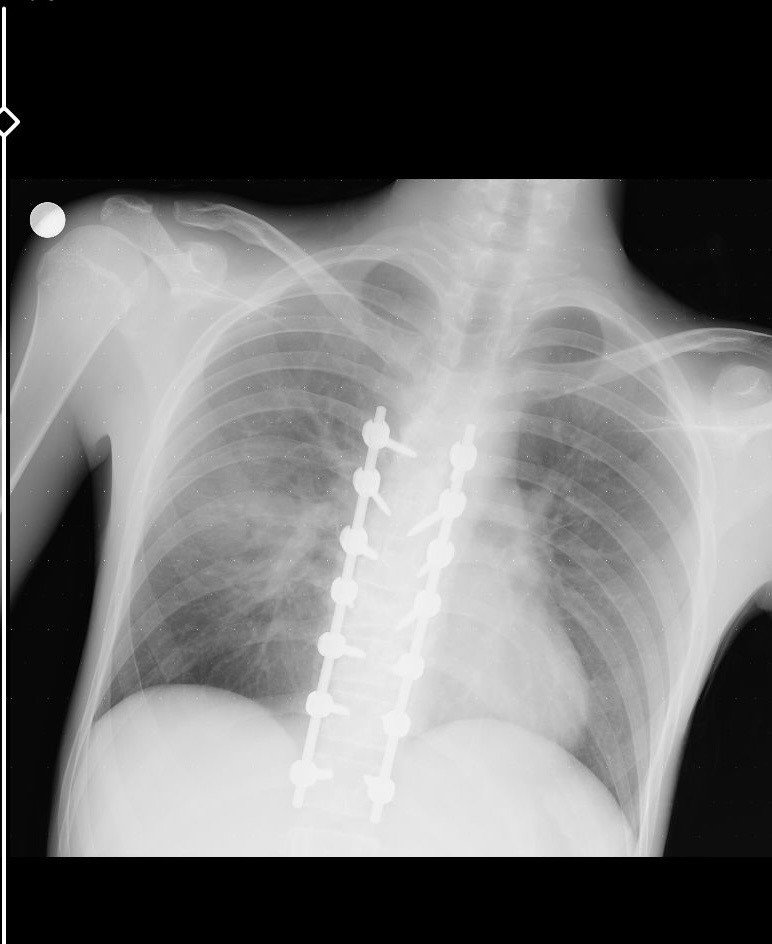

"Beş gün entübe edildi. Ne olacağı belli değildi çıkmama ihtimali vardı. Şükürler olsun doktorlarımız ve Rabbim sayesinde entübeden çıktık. Hatta ciğerin birisinde infilak vardı; ciğer sorunumuzdan dolayı özellikle yoğun bakımda entübediydik. Beş günün sonunda ciğerleri toparlamaya başladı; entübeden çıkarttılar. Solunumu normale döndü. Sırayla sağlığı yerine gelmeye başladı. Bir hafta sonra kolundan ameliyat oldu platin koydular. Omurilikten ameliyat olduk. Omuriliğinde ilk röntgende tek kırık gördüler; üç kemiği birbirine bağlayacaklardı. Sonradan ikinci röntgende üç kırık olduğunu gördük; yedi kemiği birbirine bağladılar. Omuriliğe platin takıldı. 14 tane civatamız var. Şükürler olsun doktorlarımıza, Allah razı olsun. Evladımız gayet iyi, sağlıklı, yerinde. Artık işte suratta, çenede, burunda, elmacık kemiklerinde parçalı kırıklarımız var. Osman Gazi Fakültesi'nde Allah'ın izniyle buradaki hocalarımıza, önce Rabbim'e sonra hocalarımıza emanet çocuğumuz. İnşallah daha iyi olacağız; ben kendi adıma söylüyorum. Çocuğuma, her motora bindiklerinde sürekli kask ve montlarını giymelerini tembihliyordum. Giymediklerinde fırça atıyordum. Eskişehir'de birçok yerde tanınırız, tanırlar. Sevenimiz, eşimiz, dostumuz çok; uyarırlar, telefon gelir, haber verirler. Her duyduğumda, gördüğümde söylerim. Sağ olsun, çocuğum da o gün beni dinlemiş, kaskını takmış. Şükürler olsun ki takmış; takmasaydı o gün, o kazada belki çocuğumuzu kaybederdik."